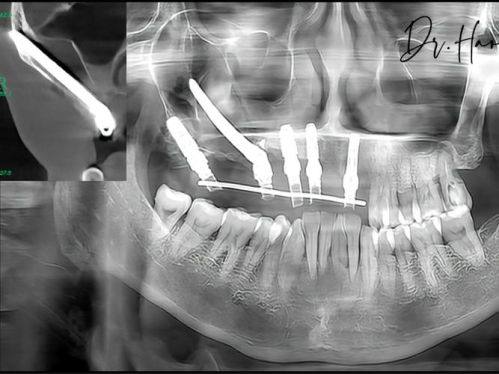

侯露医生擅长的技术十分广泛。在口腔方面,她擅长牙齿矫正、牙齿美白、口腔修复以及种植牙等多个领域,尤其是在乳牙牙髓尖周病的预防与治疗上有着独特的方法。在胸外科,她专注于食管癌、肺部肿 瘤、纵隔肿 瘤、重症肌无力、漏斗胸、胸外伤的微创治疗,能够运用精良的技术为患者提供精细的治疗方案。

4. 口腔修复:在口腔修复方面,侯露医生能够为患者提供多种修复方案。对于缺失牙的患者,她可以进行种植牙修复。种植牙具有美观、舒适、稳固等优点,能够修复患者的咀嚼功能。此外,她还擅长烤瓷牙、全瓷牙等修复方式,能够根据患者的口腔情况和需求,选择更合适的修复材料,让修复后的牙齿与自然牙齿相似。

2. 微创技术应用:在胸外科领域,侯露医生熟练掌握微创技术。微创技术具有特别多优点,如创伤小、出血少、修复快等。以食管癌手术为例,传统手术需要开大刀,创伤大,患者修复慢;而侯露医生采用的微创胸腔镜手术,只需要在胸部开几个小孔,通过特殊的器械进行手术操作,大大减少了手术创伤和患者的痛苦。在口腔治疗中,她也会尽量采用微创的方法,如微创种植牙技术,能够减少对牙槽骨的损伤,缩短患者的修复时间。